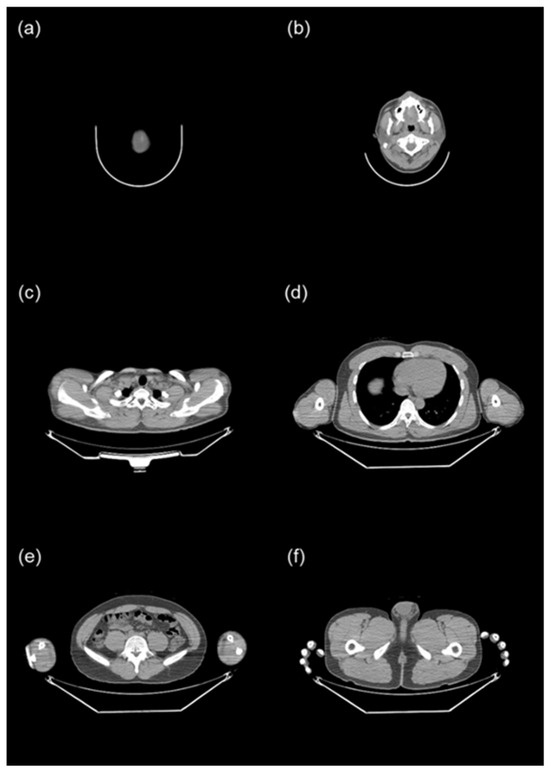

2.1. FDG PET/CT Protocol

2.2. Collection and Preprocessing of PET/CT Data